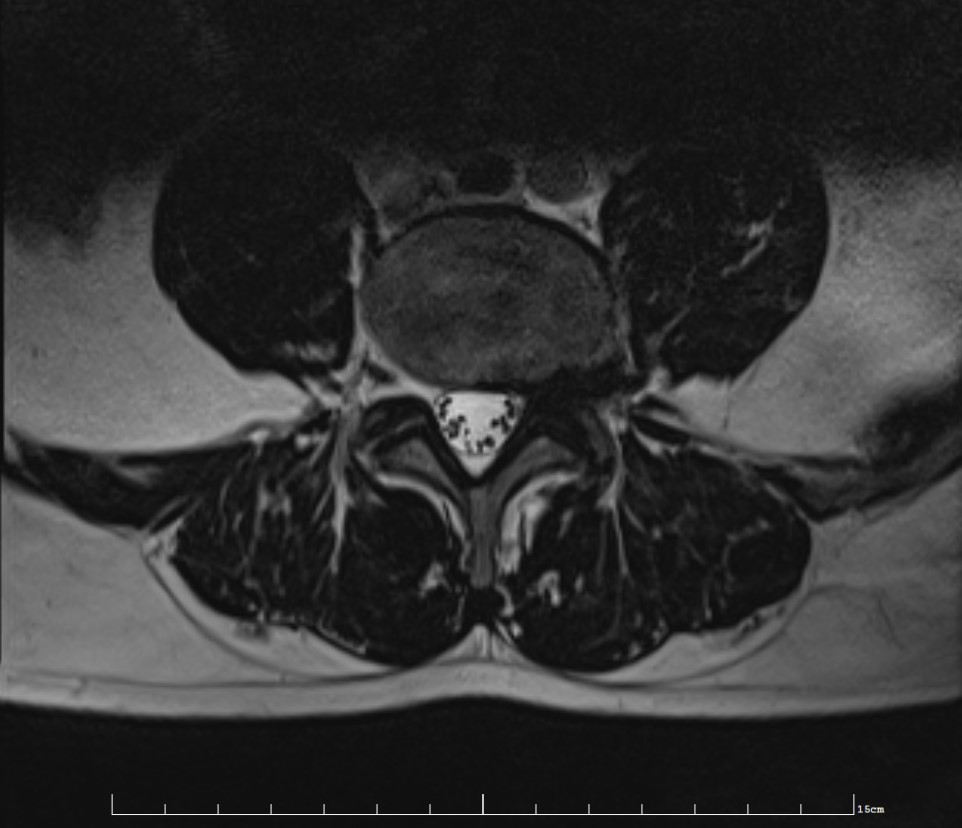

Les patients inclus FIG. 1. — Images pré-opératoires : a) tomodensitométrie, b) IRM séquence T2. Hernie discale extraforaminale gauche. FIG. 1. — Preoperative a) CT-scan, b) MRI T2-weighted. Left L5-S1 extraforaminal disc herniation. ab 586 S. FUENTES et al. Neurochirurgie n'avaient pas d'antécédents de chirurgie discale à l.. Disc herniation. Disc herniation is displacement of disc material like nucleus pulposus, parts of the annulus fibrosus and cartilage, beyond the limits of the intervertebral disc space. It can be focal ( < 90º), broad-based ( 90º-180º) or caused by bulging of the disc (> 180º).